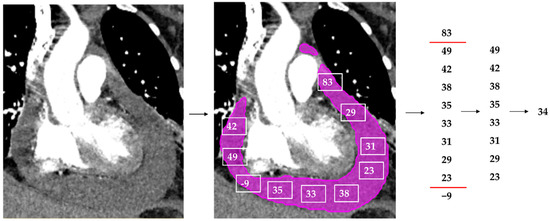

2.7. The Model’s Output